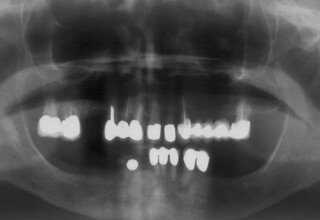

Ολική Στοματική Αποκατάσταση σε Εμφυτεύματα με διαφορετική προσέγγιση στην Άνω και Κάτω Γνάθο

Κάτω γνάθος: εξαγωγές, άμεση τοποθέτηση εμφυτευμάτων και άμεση φόρτιση(την ίδια ημέρα) με προσωρινή γέφυρα

Άνω γνάθος: σταδιακές εξαγωγές, σταδιακή τοποθέτηση εμφυτευμάτων και σταδιακή ενσωμάτωση τους στην προσωρινή γέφυρα ώστε η ασθενής να μην μείνει ούτε μια ημέρα χωρίς αποκατάσταση. Στόχος η συνεχής λειτουργική και αισθητική αποκατάσταση της ασθενούς χωρίς άμεση φόρτιση των εμφυτευμάτων λόγω ανατομικών ιδιαιτεροτήτων.

Χρησιμοποιήθηκαν παλαιές χαμογελαστές φωτογραφίες της ασθενούς γιατί είχε χαθεί τελείως το φυσικό σχήμα των δοντιών εξαιτίας των πολλαπλών προσθετικών προσπαθειών που είχαν γίνει στο παρελθόν. Μεταφέρθηκε στην προσωρινή γέφυρα η σχέση των φυσικών δοντιών μεταξύ τους άλλα και με τα χείλη. Δοκιμάστηκε η φώνηση και η μάσηση με δυο διαφορετικές προσωρινές άνω γέφυρες και εκτιμήθηκε η αισθητική απόδοση τους. Αφού επιτεύχθηκαν σε βαθμό ικανοποιητικό η φώνηση και η αισθητική εμφάνιση της οδοντοφυΐας, η προσωρινή αποκατάσταση χρησιμοποιήθηκε ως οδηγός για την τελική.